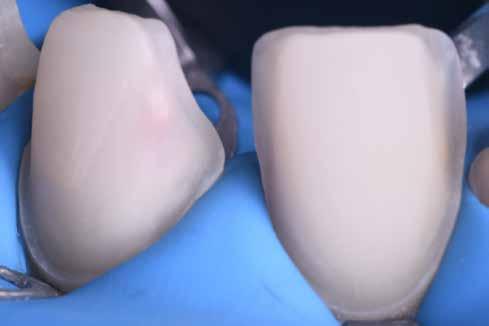

A héjak átadását követően kialakuló állapot valósághű módon történő bemutatása érdekében próbapasztát alkalmaztunk (Try-In-Paste; Variolink® Esthetik Try-In-Paste, Ivoclar Vivadent) (11. ábra). A próba során ellenőrizzük a héjak színét, formáját és transzparenciáját. A próbapaszta alkalmazásának egyik lényeges pontja, hogy a paszta színe egyezzen meg a végleges beragasztás során alkalmazni kíván ragasztóanyag színével. A héjak végleges rögzítése során mindig adhezív rendszereket használunk.

A preparálást nem igénylő héjak általában nagyon vékonyak, és sajnálatos módon ebből adódóan a végleges átadásuk előtt történő előkészítés során könnyen eltörhetnek. Csupán a páciensek saját fogain történő végleges rögzítés révén kapják meg azt az alátámasztottságot, amely a végleges töréssel szembeni ellenálló képességüket biztosítja. A fogpróba során a héjakat egyesével a fogakra helyezzük, és ellenőrizzük a pontos illeszkedésüket, valamint az approximális kontaktpontok megfelelőségét. Amenynyiben mindent rendben találtunk, úgy hozzákezdhetünk a héjak adhezív módszerrel történő rögzítéséhez szükséges előkészületek elvégzéséhez. Első lépésként a héjak elhorgonyzásul szolgáló fogak abszolút izolálását követően, meggyőződünk a ragasztási felület leszáríthatóságáról. Ezt követően az adhezív rögzítés során felhasznált fogfelszínt – az alkalmazni kívánt adhezív rendszer